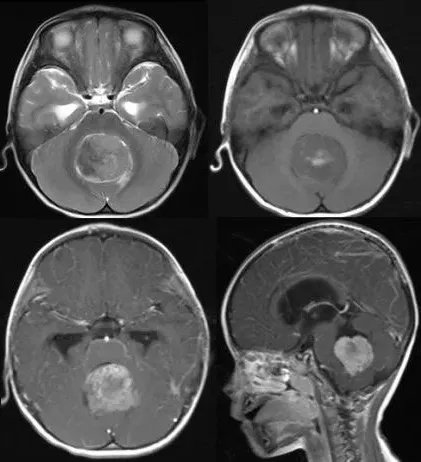

髓母细胞瘤典型影像